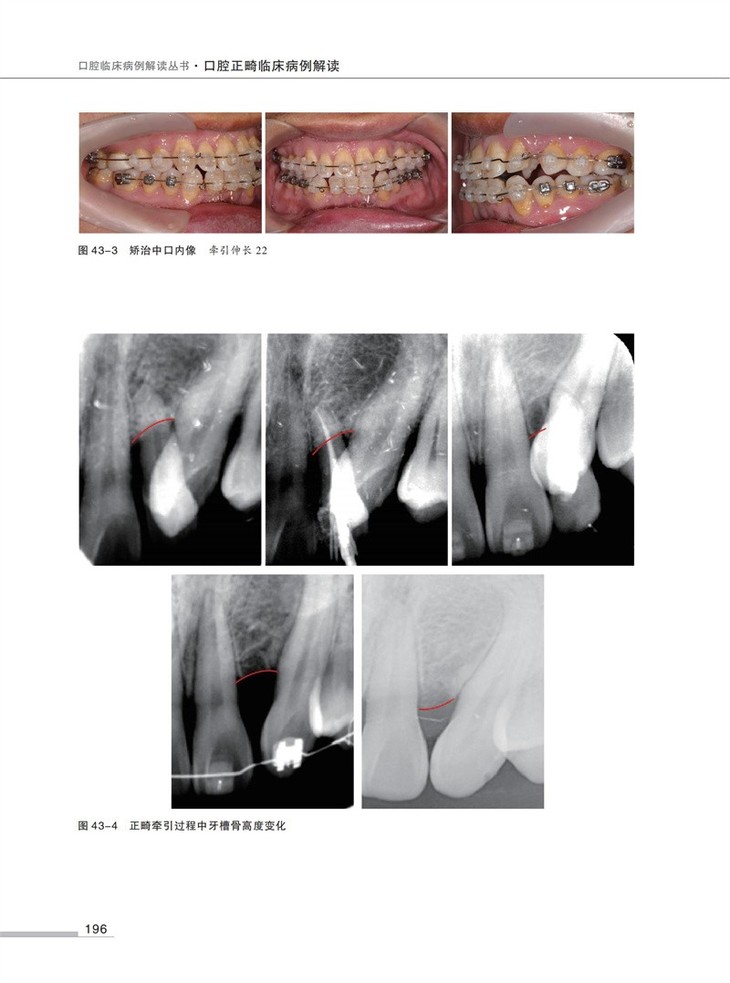

54例正畸经典病例,每例病例均包含检查、模型分析、诊断、治疗计划、弓丝序列、矫治结果及矫治体会等基础信息。

1500余幅精美图片,直观清晰,易于理解。

全书共分为7部分54例病例,每部分依次讨论安氏I类错矫治、安氏II类错矫治、安氏III类错矫治、正畸-正颌矫治严重骨型错畸形、多学科联合矫治复杂错畸形、舌侧矫治、隐形矫治。在病例的选择中兼顾高角、低角患者,骨性、牙性问题,手术优先、普通顺序的手术治疗,力求尽可能全面地展示临床上常见的病例种类和治疗方法。本书精选病例,讨论全面,完整地展示出从诊断分析到治疗实践的临床思维全过程。